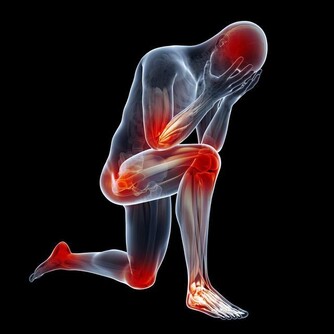

雖然現在已步入溫暖的冬季,但早晚溫度較低,因此應該注意防寒保暖,因為寒冷,可以使交感神經興奮增強,導致尿道內壓增加而引起逆流,前列腺管也因收縮而排泄障礙,產生充血,使症狀反复或加重。